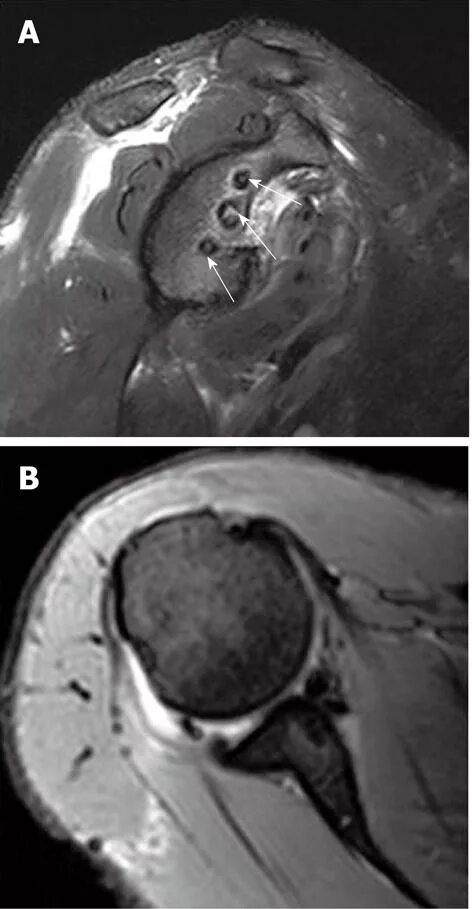

Изменение фиброзной губы гленоида